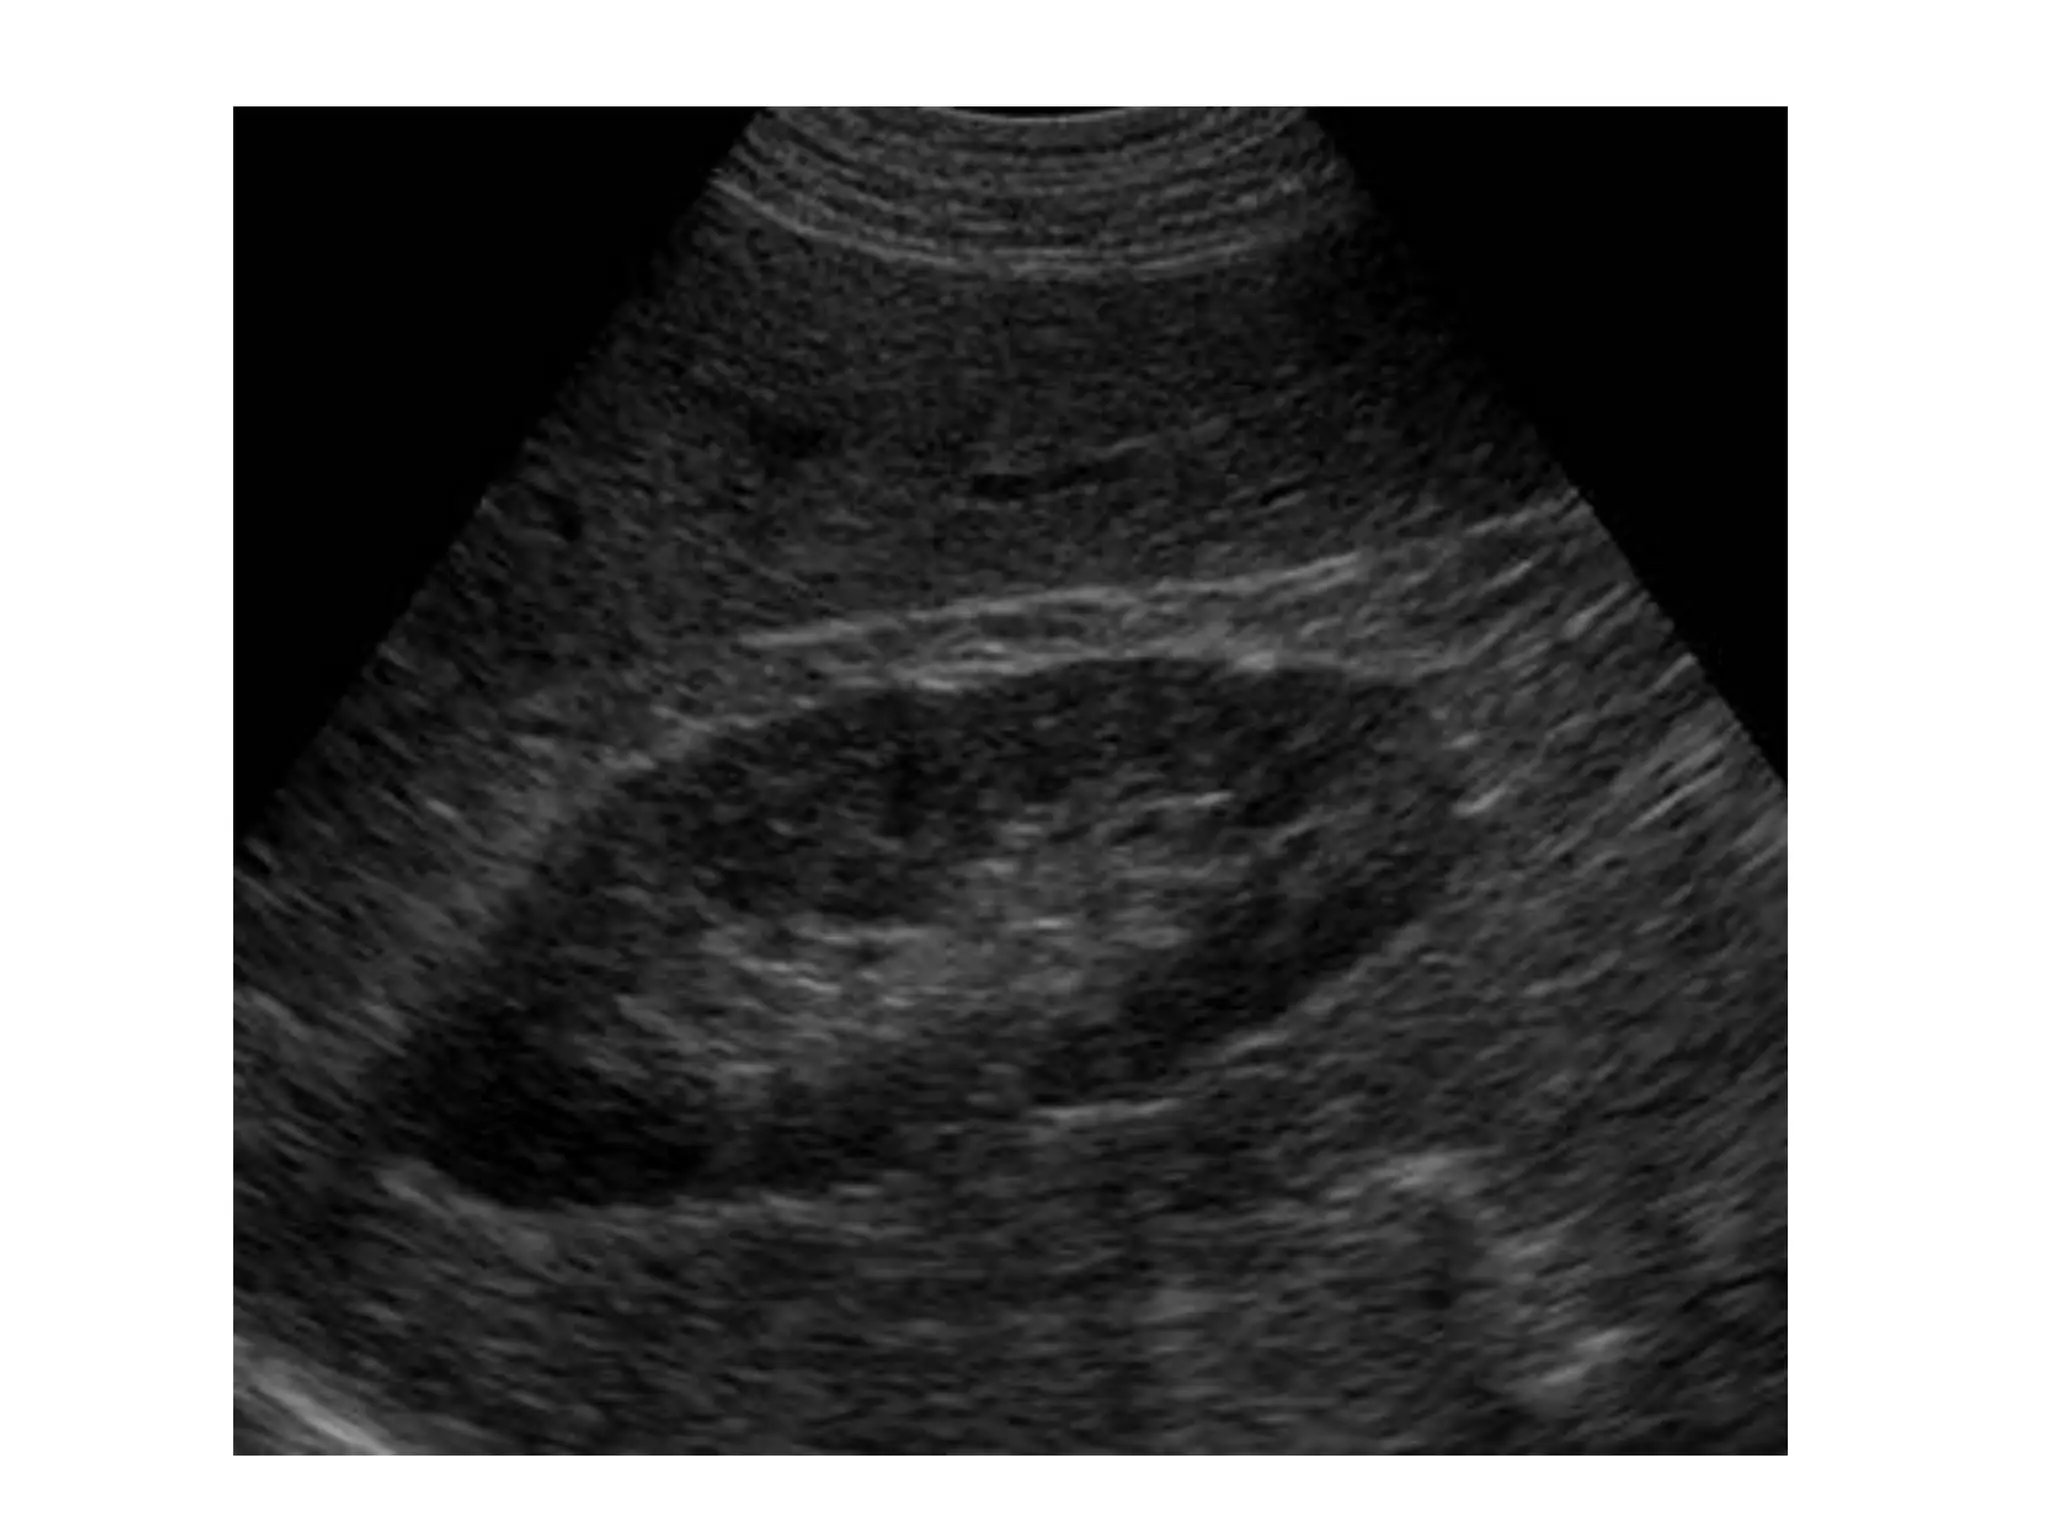

Clasificacion de la hidronefrosis

Grado 0: Riñón normal sin hidronefrosis

Grado 1: Pelvis renal ligeramente dilatada sin ectasia calicial

Grado 2: Pelvis renal moderadamente dilatada con ectasia calicial leve

Grado 3: Pelvis renal grande, cálices dilatados y parénquima normal

Grado 4: Pelvis renal muy grande, cálices grandes y dilatados

y adelgazamiento del parénquima renal.

Mejor prueba de imagen

Ultrasonido para diagnostico inicial

TC+C para la resolucion de problemas